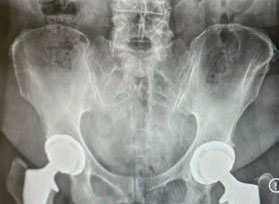

He could plainly see the cause of Cheryl’s pain. “X-rays showed degeneration in her hips that was very advanced,” he says. “She had no cartilage left. It was bone-on-bone.”

Cheryl’s anatomy suggested she also may have been born with subtle hip dysplasia—a misalignment in the joint that can predispose people to arthritis later in life.

In each hip, Dr. Kayiaros installed an implant made of materials such as titanium, medical-grade polyethylene and ceramic. Implants allow the joint to function smoothly, with certain surfaces roughened so bone more readily grows into them for strength and stability.